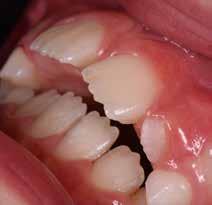

Presentazione del caso > F.V, bambino di cinque anni, presenta una malocclusione di II Classe scheletrica, III Classe dentale molare e canina destra e sinistra, morso inverso anteriore. Le arcate dentali mostrano usura degli elementi dentari anteriori a causa dell’occlusione patologica. Le linee mediane, superiore ed inferiore, sono centrate; il frenulo labiale superiore patologico per un’eccessiva estensione inter-incisale.

Dall’esame clinico si evince la III Classe dentale, l’inversione anteriore e l’over-jet negativo.

Una volta ottenuta la correzione del rapporto molare ed incisale, l’apparecchio elastodontico verrà portato dal paziente solo durante la notte per stabilizzare il risultato ottenuto e guidare l’eruzione degli elementi dentari per un totale di quattordici mesi di terapia. ad inizio trattamento :

Considerazioni > L’analisi cefalometrica ad inizio trattamento dimostra la II Classe scheletrica con protrusione del mascellare superiore e prognazia mandibolare; tendenza alla crescita verticale. L’esame clinico evidenzia una protrusione mandibolare funzionale.

55 54 ESTETICA FUNZIONE POSTURA Valori cefalometrici ad 1 anno di terapia : ANB ANB 3,8 Posizione del Mascellare SNA 91.40 Posizione della Mandibola SNB 87,60 Angolo Articolare SArGo 155,00 Angolo Goniaco ArGoMe 122,00 Angolo incisivo inf^Corpo madibolare IiMand 80,20 Angolo incisivo Sup^Base Cranica Ant. IsCran 111,05 Angolo Interincisivo II 138,00 72, 73 _ Over-bite e over-jet. 74 _ Immagine laterale destra. 75 _ Immagine laterale sinistra. Considerazioni > La terapia precoce di tali malocclusioni è di primaria importanza in quanto impedisce la formazione di malocclu-